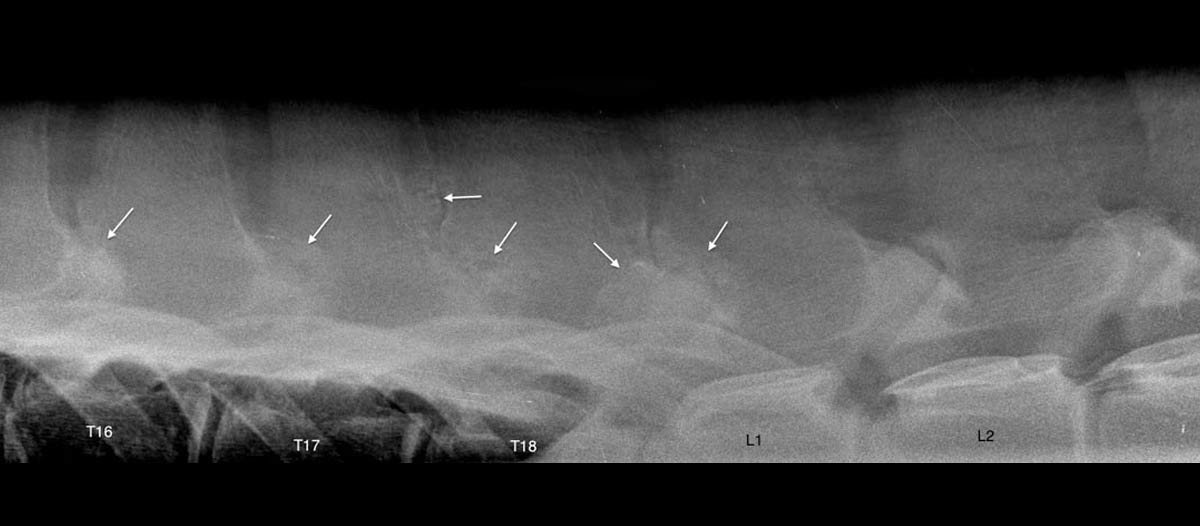

Radiologie

Radiologie bestaat al lang, maar toch blijft de technologie evolueren. EquiSound beschikt over digitale radiografie, gecombineerd met een röntgenbuis van 80.000 Watt (80kV). Zo maken wij kwalitatieve beelden van het volledige paard, inclusief nek, rug en hoofd.

Bucky Systeem

Info volgt